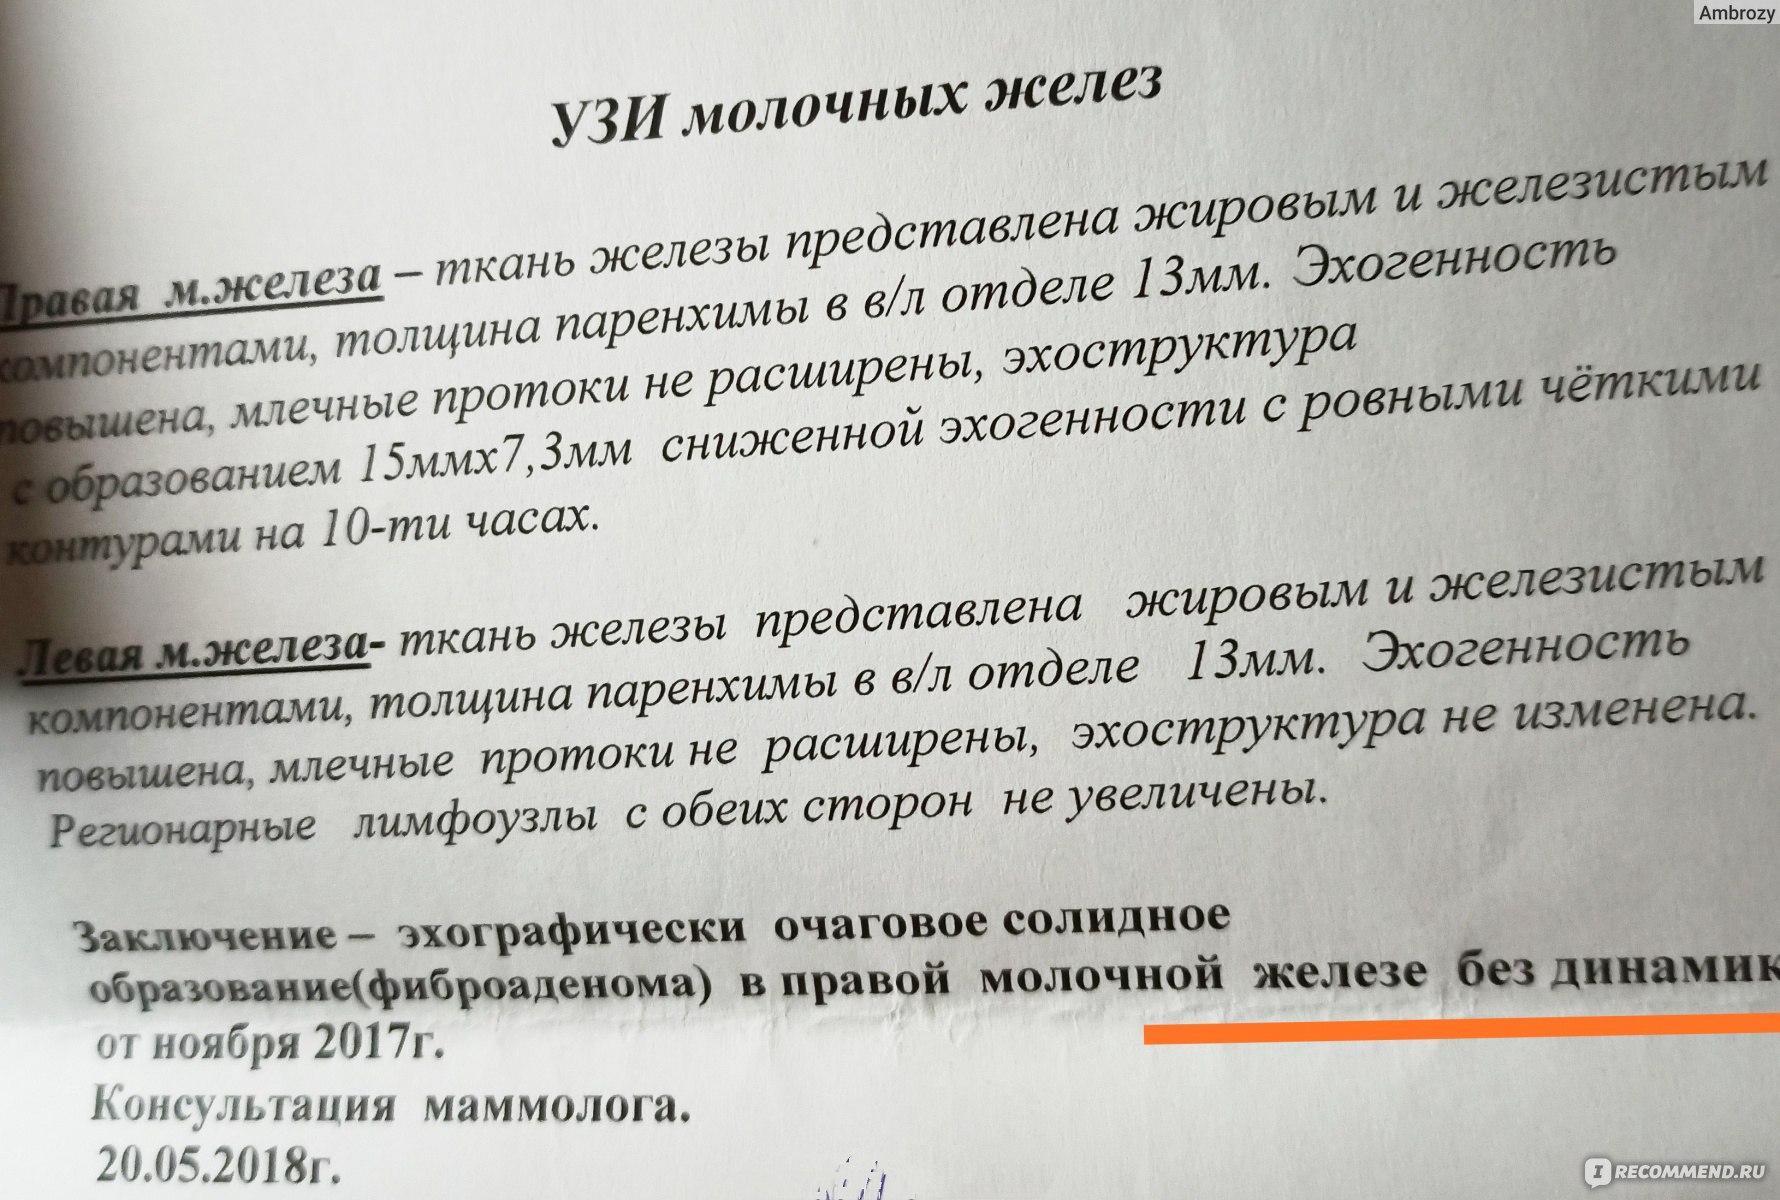

Фиброзно-кистозная мастопатия на УЗИ